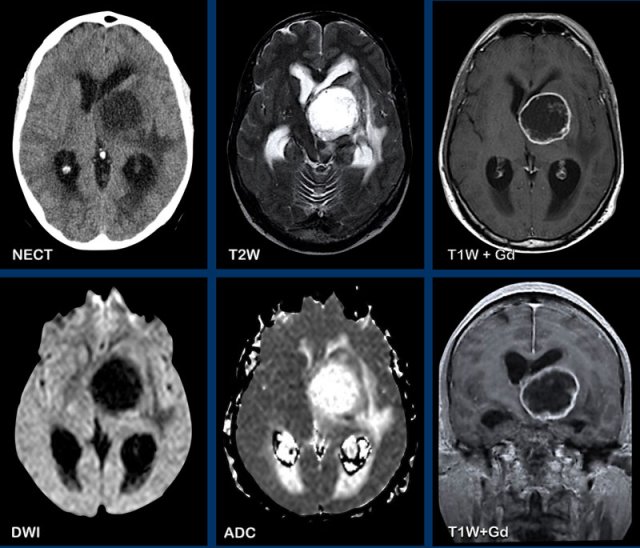

These images are of a 76-year old woman, who was confused after a fall.

First look at the images and then continue reading.

Question:

- What is the most likely diagnosis?

- Which findings are typical for this diagnosis?

The findings are:

- Hyperdense lesion on the NECT with some vasogenic edema.

- MR shows multiple lesions with solid enhancement and diffusion restriction.

- On T2W the lesions show a low signal intensity

- One lesion is located in the corpus callosum and another one is periventricular.

All these findings are typical for a primary CNS lymphoma, which is different from a systemic lymphoma.

These tumors make up for 6-7% of all CNS tumors and the histology is a B-cel NHL.

They are mostly located periventricular subependymal, in the corpus callosum and in the basal ganglia.

Always think lymphoma in a solid enhancing lesion which is located near the ventricles.

The hyperdense appearance on CT and the slight hypointensity on T2W-imaging, as well as the restricted diffusion are attributed to the dense cellularity of the lymphomatous tissue.

In immuno-compromised patients the enhancement can be ring-like.

This patient has a lot of edema, but in many cases the edema is very limited.